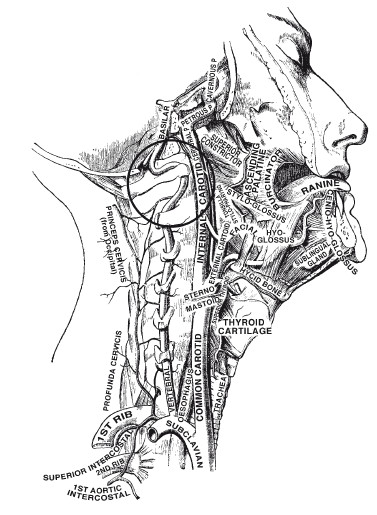

Найтингейл была убеждена, что и другие значимые медицинские решения следует обосновывать подобным образом, поэтому боролась за учреждение Королевской военно-медицинской комиссии, в которую лично передала несколько сотен страниц подробных статистических сведений. В те времена, когда не принято было приводить даже таблицы данных, Флоренс Найтингейл чертила еще и цветные диаграммы, которые смотрелись бы вполне уместно в современной презентации на заседании совета директоров. Она даже изобрела новую версию круговой диаграммы (см. рисунок на странице 53), хорошо отображающую ее данные. Найтингейл осознала, что иллюстрирование статистических данных поможет донести ее доводы до политиков, как правило, несильно подкованных в математике.

Полярная диаграмма[9] Флоренс Найтингейл, иллюстрирующая смертность во время Крымской войны в британской армии на востоке, апрель 1854 – март 1855